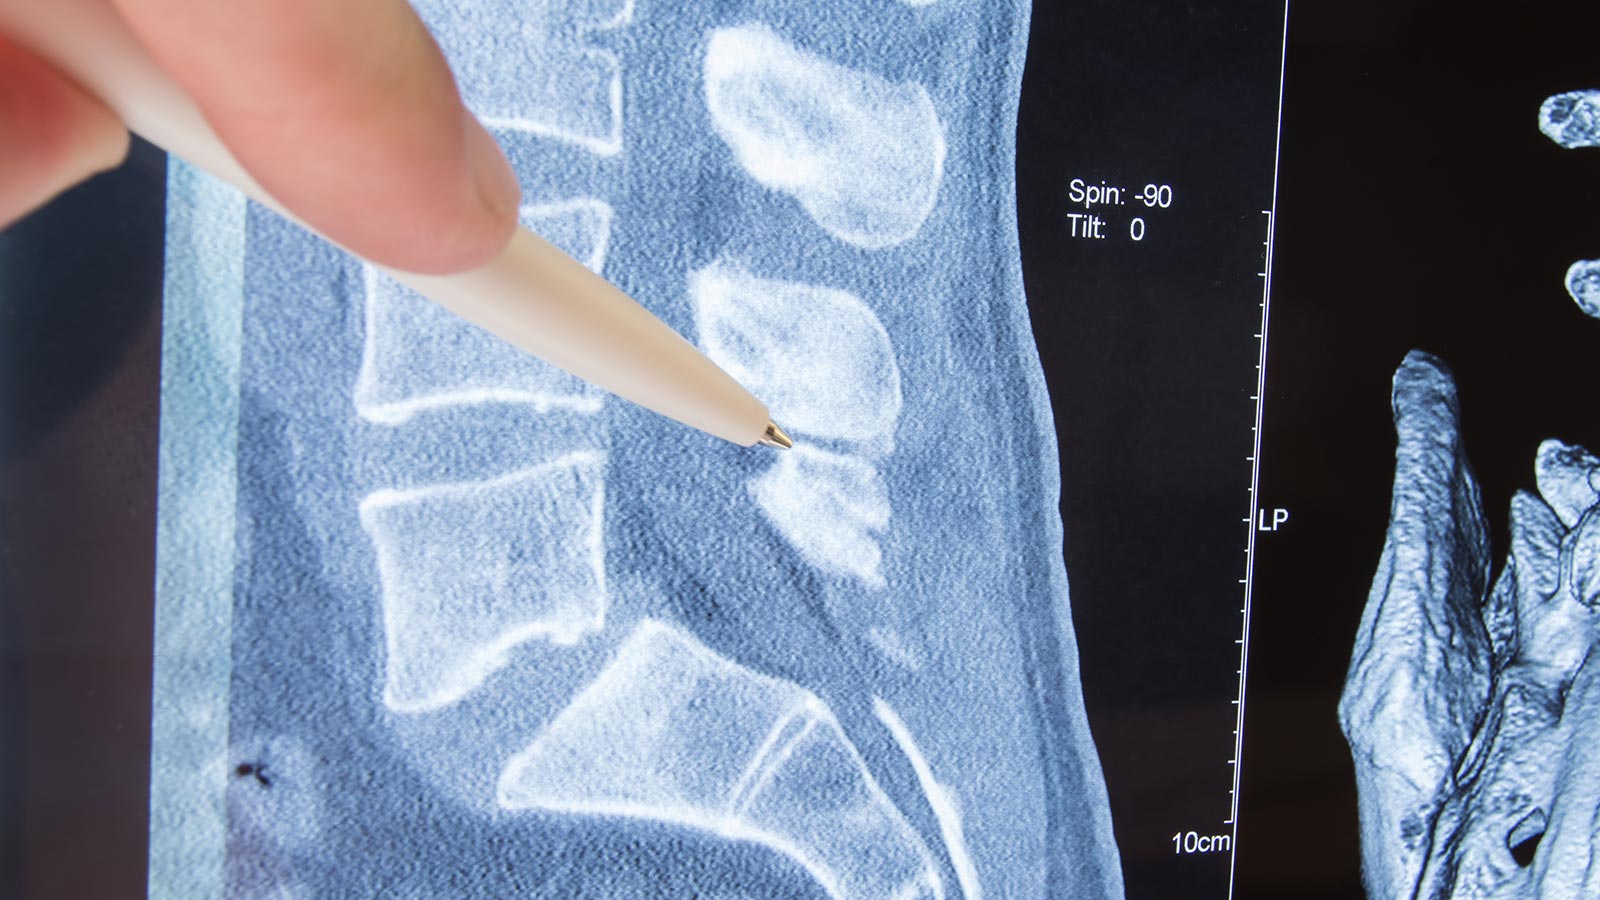

Habitualmente, la causa de la ciática se debe a la compresión del nervio espinal debido a algún problema de la columna vertebral, ya sea en las vértebras (artrosis), en los discos intervertebrales (protrusión o hernia discal) o en ambos.